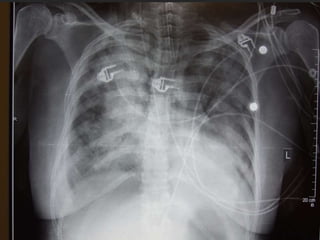

 Diffuse infiltrates

 CXR – diffuse alveolar infiltrates

 Severe endof the spectrum of acute lung injury  Acute and persistent lung inflammation with increased vascular permeability  Diffuse infiltrates  Hypoxemia – paO2/FiO2 <200  (i.e. pO2 70 / FiO2 0.5 = 140)  No clinical evidence of elevated left atrial pressure (PCWP <18 if measured)

 Early  Incitingevent, pulmonary dysfunction (worsening tachypnea, dyspnea, hypoxemia)  Nonspecific labs  CXR – diffuse alveolar infiltrates  Subsequent  Improvement in oxygenation  Continued ventilator dependence  Complications  Large dead space, high minute ventilation requirement  Organization and fibrosis in proliferative phase

 Macrobarotrauma  Pneumothorax,interstitial emphysema, pneumomediastinum, SQ emphysema, pneumoperitoneum, air embolism  ? resulting from high airway pressures, or just a marker of severe lung injury  Higher PEEP predicts barotrauma